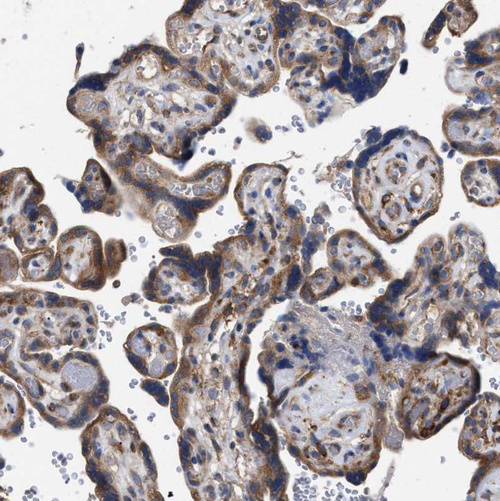

Immunohistochemistry analysis in human duodenum and skeletal muscle tissues using HPA022015 antibody. Corresponding CDR2L RNA-seq data are presented for the same tissues.